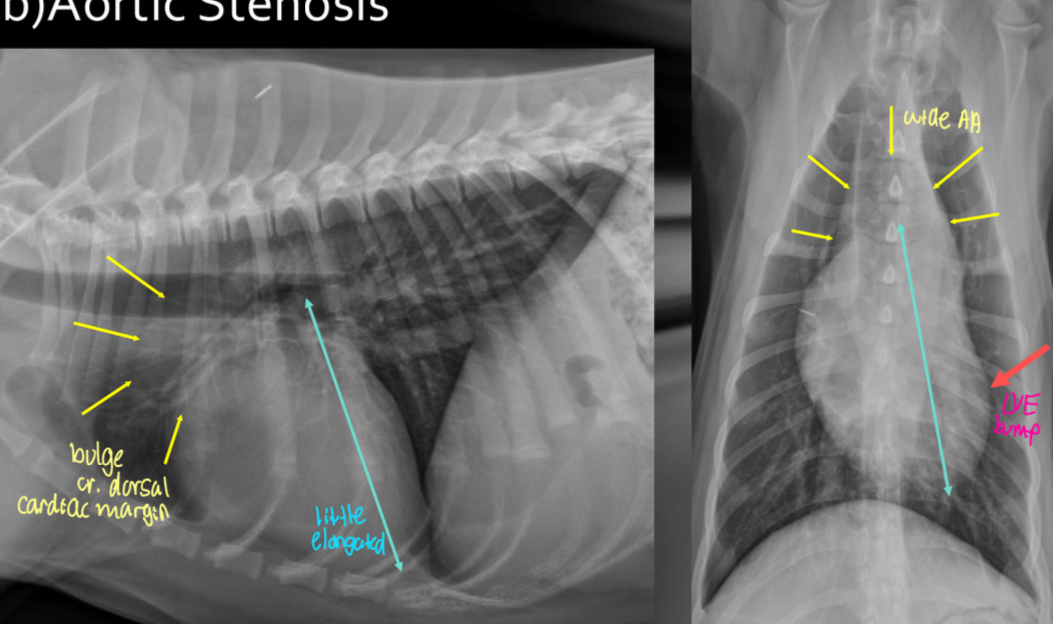

What disease does this dog have

Aortic stenosis

Roentgen signs of aortic stenosis

-survey rads could be NORMAL

-LH enlargement (LVE ± LAE) from PRESSURE OVERLOAD

-elongated cardiac silhouette

-AA bump

-low incidence of LHF

Pathogenesis of aortic stenosis

1.subaortic abnormality

2.left ventricular hypertrophy

3.focal dilation of AA

What does the angiocardiography highlight in aortic stenosis

-AA bulge

-increased cardiac waist

-left ventricular hypertrophy

-narrowing of aortic outflow tract

-post stenotic dilation of AA

± mitral regurg